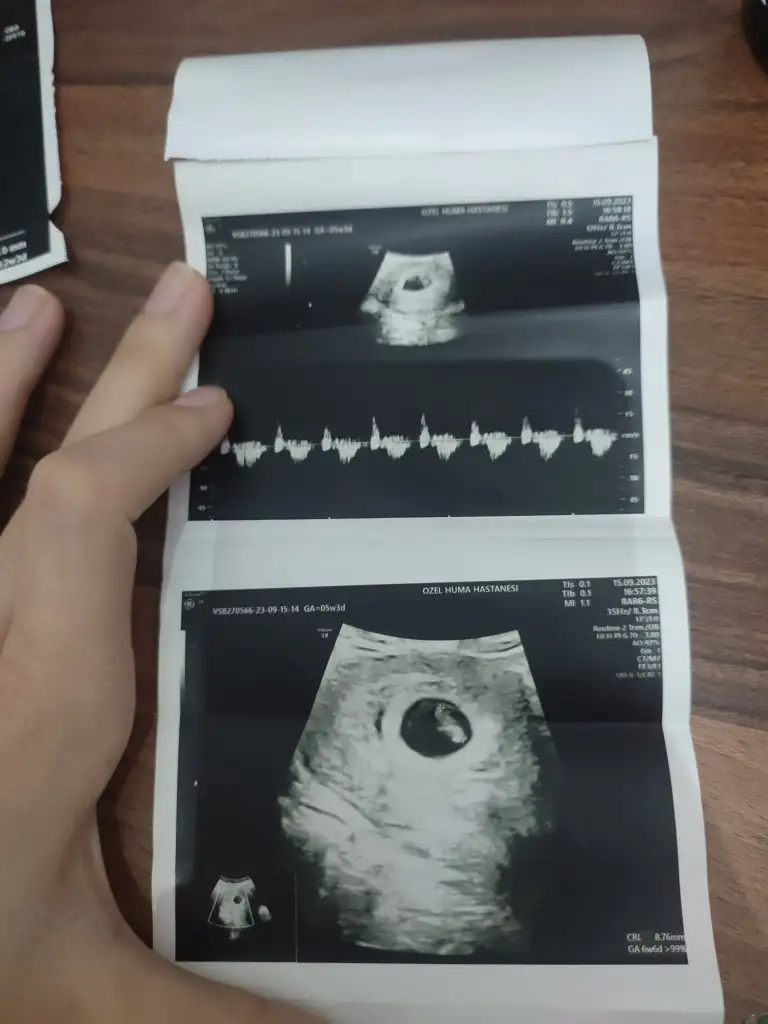

Ya benim içinde tahmin yapar mısınız? İlk resim 12 hafta ikinci ve üçüncü 6 hafta iken son fotoğrafta 14 hafta. Sizce cinsiyeti ne belli oluyor mu?

Canım konum her zaman dogru çıkmıyor 12. Haftada az çok belli olur. İlk görüntü karından degil mi çünkü vajinalda degişiyor. Allahım inşallah gönlündekini saglıkla nasip etsin sana bunu canı gönülden diliyorum bende hamileyim ve iki kızım var buda erkek olsun çok istiyorum ama banada hep kız yorumu yaptılar. Bende erkek hissediyorum ama galiba istedigim için diyorum